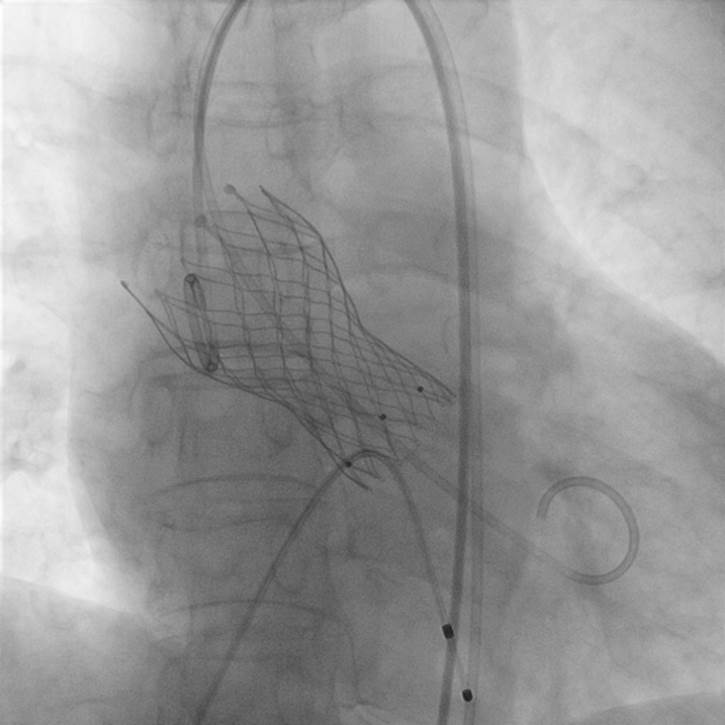

△TAVR术人工主动脉瓣膜

△TAVR术后影像

10月17日,在麻醉科、超声科等多学科团队的协同配合下,心血管内科手术团队精准操作,顺利为患者植入人工主动脉瓣。术后复查显示,瓣膜功能良好,心脏泵血能力显著提升,患者胸闷、心悸症状完全消失,活动能力恢复正常。